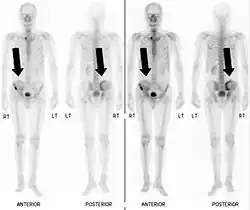

Bone scintigraphy

Bone scintigraphy showing black marks where pelvic bone damage has occurred.

Also known as a bone scan, bone scintigraphy involves the injection of a small amount of radioactive tracer into the bloodstream. This tracer decays and emits radioactive energy which can be detected by a special camera. The camera produces a black and white image where areas shown as dark black indicate bone damage of some kind. If there is a black spot in the lumbar vertebrae (e.g. L5) this indicates damage and potentially spondylolysis. If this test is positive, a CT scan is usually ordered to confirm spondylolysis.[16]